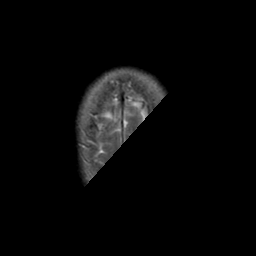

Stroke:T2-weighted MR #2 -- Slice #23

[Home][Help][Clinical] Slice 23